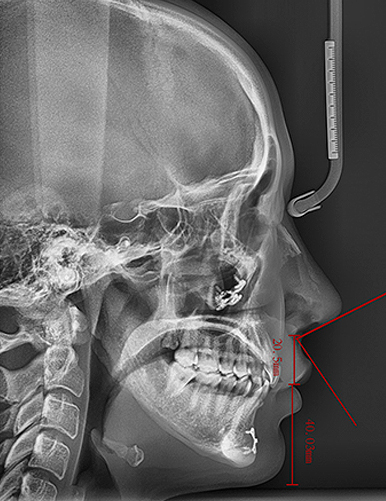

Under the expertise of Dr. Seungil Chung, each patient’s skeletal structure, muscle movement, and lip shape are analyzed in detail to achieve an ideal nasolabial angle and side profile. This is not just a correction—it is a harmonious redesign of the entire face.

Individual skeletal structure, muscle movement, and lip shape are analyzed to achieve the most ideal nasolabial angle and side profile.